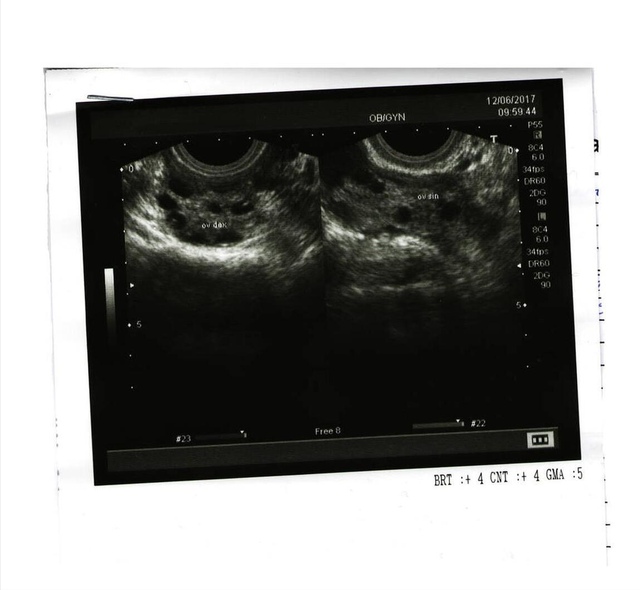

晓茹是一名高一学生,一天上体育课时,她觉得腹部疼痛难忍,老师把她送到医院。查小便、验肝功能都没有问题,通过B超检查,才发现她的肚子居然长了个比棒球还大的卵巢肿瘤!

卵巢囊肿的发病与环境因素、生活习惯、精神状态等有关,但与婚否没有直接关系。未婚女性发现腰围和腹部异常,如有月经失调、经量减少甚至腹痛等症状时,而且持续无好转,应提高警惕。特别是身材偏胖的青少年女性更需注意。主要是因为青春期是卵巢发育成熟、功能旺盛时期,如乱用激素类补品、饮食不当、压力过大,卵巢都极易受到刺激,发生囊肿。对未婚女性来讲,一年一次妇科B超检查十分必要。

梁女士今年45岁,两年前单位组织体检时,得知自己的左侧卵巢上有个核桃大小的肿块,需定期复查。梁女士认为这是个小毛病,因为肿块不痛不痒,对生活和工作没有任何影响,医院还是能不去就不去。哪知道,才一年的时间,肿块越长越大,随之而来的是,梁女士的腹部渐渐隆起。她安慰自己,中年发福也正常,不会有事的。到今年8月份,她的肚子已经疯长到像怀了6个月的胎儿大小了,与此同时,腹胀、尿频、便秘、小腹疼痛变得比以前更明显了。一直害怕到医院的梁女士终于无法忍受,决定去看看。医生说:“卵巢囊肿已经发展为卵巢浆液性囊腺癌,必须进行开腹手术。”

卵巢虽小,但组织复杂,是全身各脏器肿瘤类型最多的部位。它位于盆腔深部,不易摸到,发病早期又无明显自觉症状,因此早期诊断比较困难,如为恶性确诊时70%往往已属晚期,是目前威胁女性生命最严重的三大恶性肿瘤之一。另外,虽然卵巢囊肿大多数是良性,但即使是良性的,如果长时间不给予有效治疗,囊肿继续长大至超过5厘米,转变成癌症的概率高。所以,对于被确诊患有卵巢囊肿的女性来说,积极治疗是当务之急。卵巢囊肿的症状包括:腹部肿胀不适、疼痛;小便或排便习惯改变,如频尿、便秘;长期消化不良,食欲不振,容易产生饱腹感,长期疲惫乏力,体重减轻等。这些症状通常在初期的卵巢囊肿都不明显,一般在癌症后期才会被发现。

孕早期的妇科检查及超声检查对于尽早发现卵巢囊肿非常重要。如果早期诊断,采取适当保健预防和治疗措施,可以顺利妊娠到足月分娩。孕16 ~ 22周是处理卵巢囊肿的最佳时期,此时子宫还不很大、空间有裕,一般可行剔除术。倘若在孕22周以后或妊娠晚期才发现,则尽可能等待胎儿成熟后,进行剖宫产的同时处理卵巢囊肿。

乔安怀孕7个月的时候,B超发现胎儿的腹腔内有囊性包块,直径约6厘米。一个月后,B超复查结果显示,包块比之前增大了2厘米。究竟是什么东西长在还未出生的宝宝肚子里呢?一家人的心里蒙上了厚厚阴影。

为了明确囊肿的具体位置,医生为宝宝做了核磁共振检查,结果显示,巨大的囊肿占据了宝宝的大半个腹腔,别的器官都被挤压到另一侧。医生说:“像她这样的病情,如果不是产前检查,就很可能要到她长大成人才会被发现,到那时其它脏器的发育不仅被影响,而且很容易因为囊肿出血坏死,然后导致卵巢坏死,引起严重后果。”随后,医生用注射器先抽了20毫升的液体出来,才将囊肿从腹腔取出。